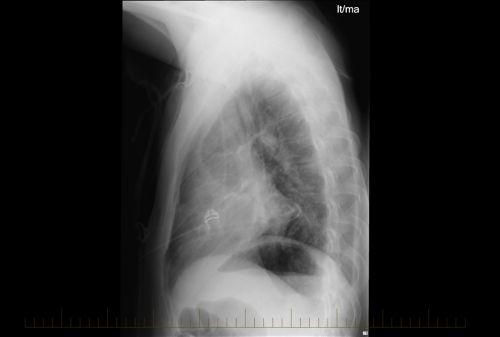

Hodgkin's Lymphoma X Ray

Hodgkin's Lymphoma X Ray. Hodgkin lymphoma (hl) is a type of lymphoma in which cancer originates from a specific type of white blood cells called lymphocytes. In hodgkin lymphoma, it is quite common to have swollen (enlarged) lymph nodes in the middle of your chest, in an area called the mediastinum. Similar lymphadenopathy can result from viral infections such as infectious mononucleosis (ebv) or cytomegalovirus (cmv). Case contributed by assoc prof frank gaillard ◉ ◈. This kind of radiation therapy won't make you radioactive. The who classifies hl into two types: Radiation therapy for hodgkin lymphoma is usually given by a large machine outside the body. Hodgkin's lymphoma is sometimes called hodgkin's disease. Which hodgkin's lymphoma treatments are right for you depends on the type and stage of your disease, your overall health, and your preferences. Finding enlarged lymph nodes helps your doctor to decide what treatment you should have. For classical hodgkin's lymphoma, radiation therapy is. Symptoms may include fever, night sweats, and weight loss. Bone marrow aspiration and biopsy (sometimes. Understand the stages of hodgkin lymphoma that determine the spread of the disease, and others terms such as b symptoms and bulky disease. This algorithm has been developed for md anderson using a multidisciplinary approach considering circumstances particular to md anderson's specific patient population, services and structure

Lymphomas are cancers that begin in the body's lymphatic system, which is part of the body's immune system. However, it may result from bone marrow involvement by imaging studies are important for accurate staging of hodgkin lymphoma. Thomas hodgkin, a british pathologist who in 1832 described several cases of people with symptoms of a cancer involving the lymph nodes. 8 218 просмотров 8,2 тыс. Case contributed by assoc prof frank gaillard ◉ ◈. For classical hodgkin's lymphoma, radiation therapy is. Lymphoma is a general name for a group of cancers that affect the lymphatic system. Assessment of traumatic brain injury online course: Finding enlarged lymph nodes helps your doctor to decide what treatment you should have. Hodgkin lymphoma was named for dr. This kind of radiation therapy won't make you radioactive. Related online courses on physioplus. Chest radiography is usually followed by a biopsy of the lymph. • typically affects young people. In hodgkin lymphoma, it is quite common to have swollen (enlarged) lymph nodes in the middle of your chest, in an area called the mediastinum. The who classifies hl into two types: Lymphoma on chest x ray. Understand the stages of hodgkin lymphoma that determine the spread of the disease, and others terms such as b symptoms and bulky disease. Lymphoma develops from an acquired (not inherited). Characteristics of classical hodgkin lymphoma. Bone marrow aspiration and biopsy (sometimes. Symptoms may include fever, night sweats, and weight loss. Which hodgkin's lymphoma treatments are right for you depends on the type and stage of your disease, your overall health, and your preferences. Treatment for hodgkin lymphoma may include: In people with hodgkin lymphoma, the cancer usually moves from one lymph node to an adjacent one. There appears to be more consensus regarding treatment for hodgkin lymphoma than other lymphoma subtypes likely because of the curative nature of treatment and the relatively young demographic. Hodgkin lymphoma (hl) is a type of lymphoma in which cancer originates from a specific type of white blood cells called lymphocytes. How is hodgkin lymphoma treated? Hodgkin lymphoma i page 1. Lymphomas are cancers that begin in the body's lymphatic system, which is part of the body's immune system. This treatment uses medicines to kill cancer cells and radiation therapy: